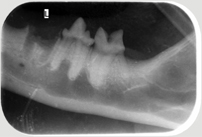

Neben der allgemeinen Untersuchung und der Untersuchung der Zahntaschen mittels Parodontalsonde sind ZAHNRÖNTGEN unumgänglich für eine komplette Diagnostik von Parodontalerkrankungen und bei Zahnresorptionen vor allem bei der Katze (FORL). Dabei werden spezielle Techniken mit Dentalfilmen wie beim Menschen verwendet.

In der Kleintier-Ordination Mittertreffling wird eine moderne digitale Entwicklung verwendet, die die Strahlenbelastung für Ihr Tier verringert. Ohne Zahnröntgen wird das Ausmaß des Knochenverlustes oft unterschätzt und bei der Katze viele Zahnresorptionen übersehen oder unterschätzt. Zudem ist bei einer wie in der Tier-Zahnheilkunde in einer Sitzung durchgeführten Wurzelbehandlung (Endodontie) eine Kontrolle durch Zahnröntgen unbedingt notwendig. Selbst Tumoren können sehr gut erkannt werden und auch die Kontrolle einer Zahnbewegung (Orthodontie) sollte durch Zahnröntgen erfolgen.

Zahnröntgen Oberkiefer Hund P4 Zahnröntgen Unterkiefer Hund normal Zahnröntgen Oberkiefer Hund dreiwurzliger P3

Katze FORL Katze FORL extrahiert